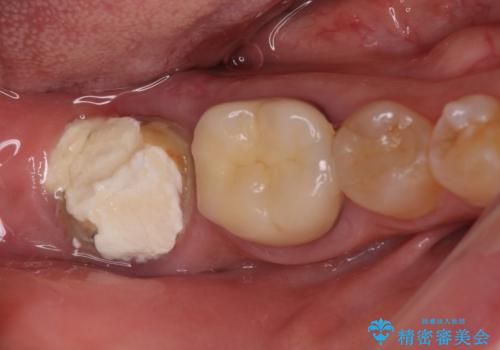

[20代男性] インプラント 失った歯の治療

![[20代男性] インプラント 失った歯の治療の症例 治療前](https://seimitsushinbi.jp/wp/wp-content/uploads/2019/11/IMG_0002-6-500x350.jpg?v=1574736384)